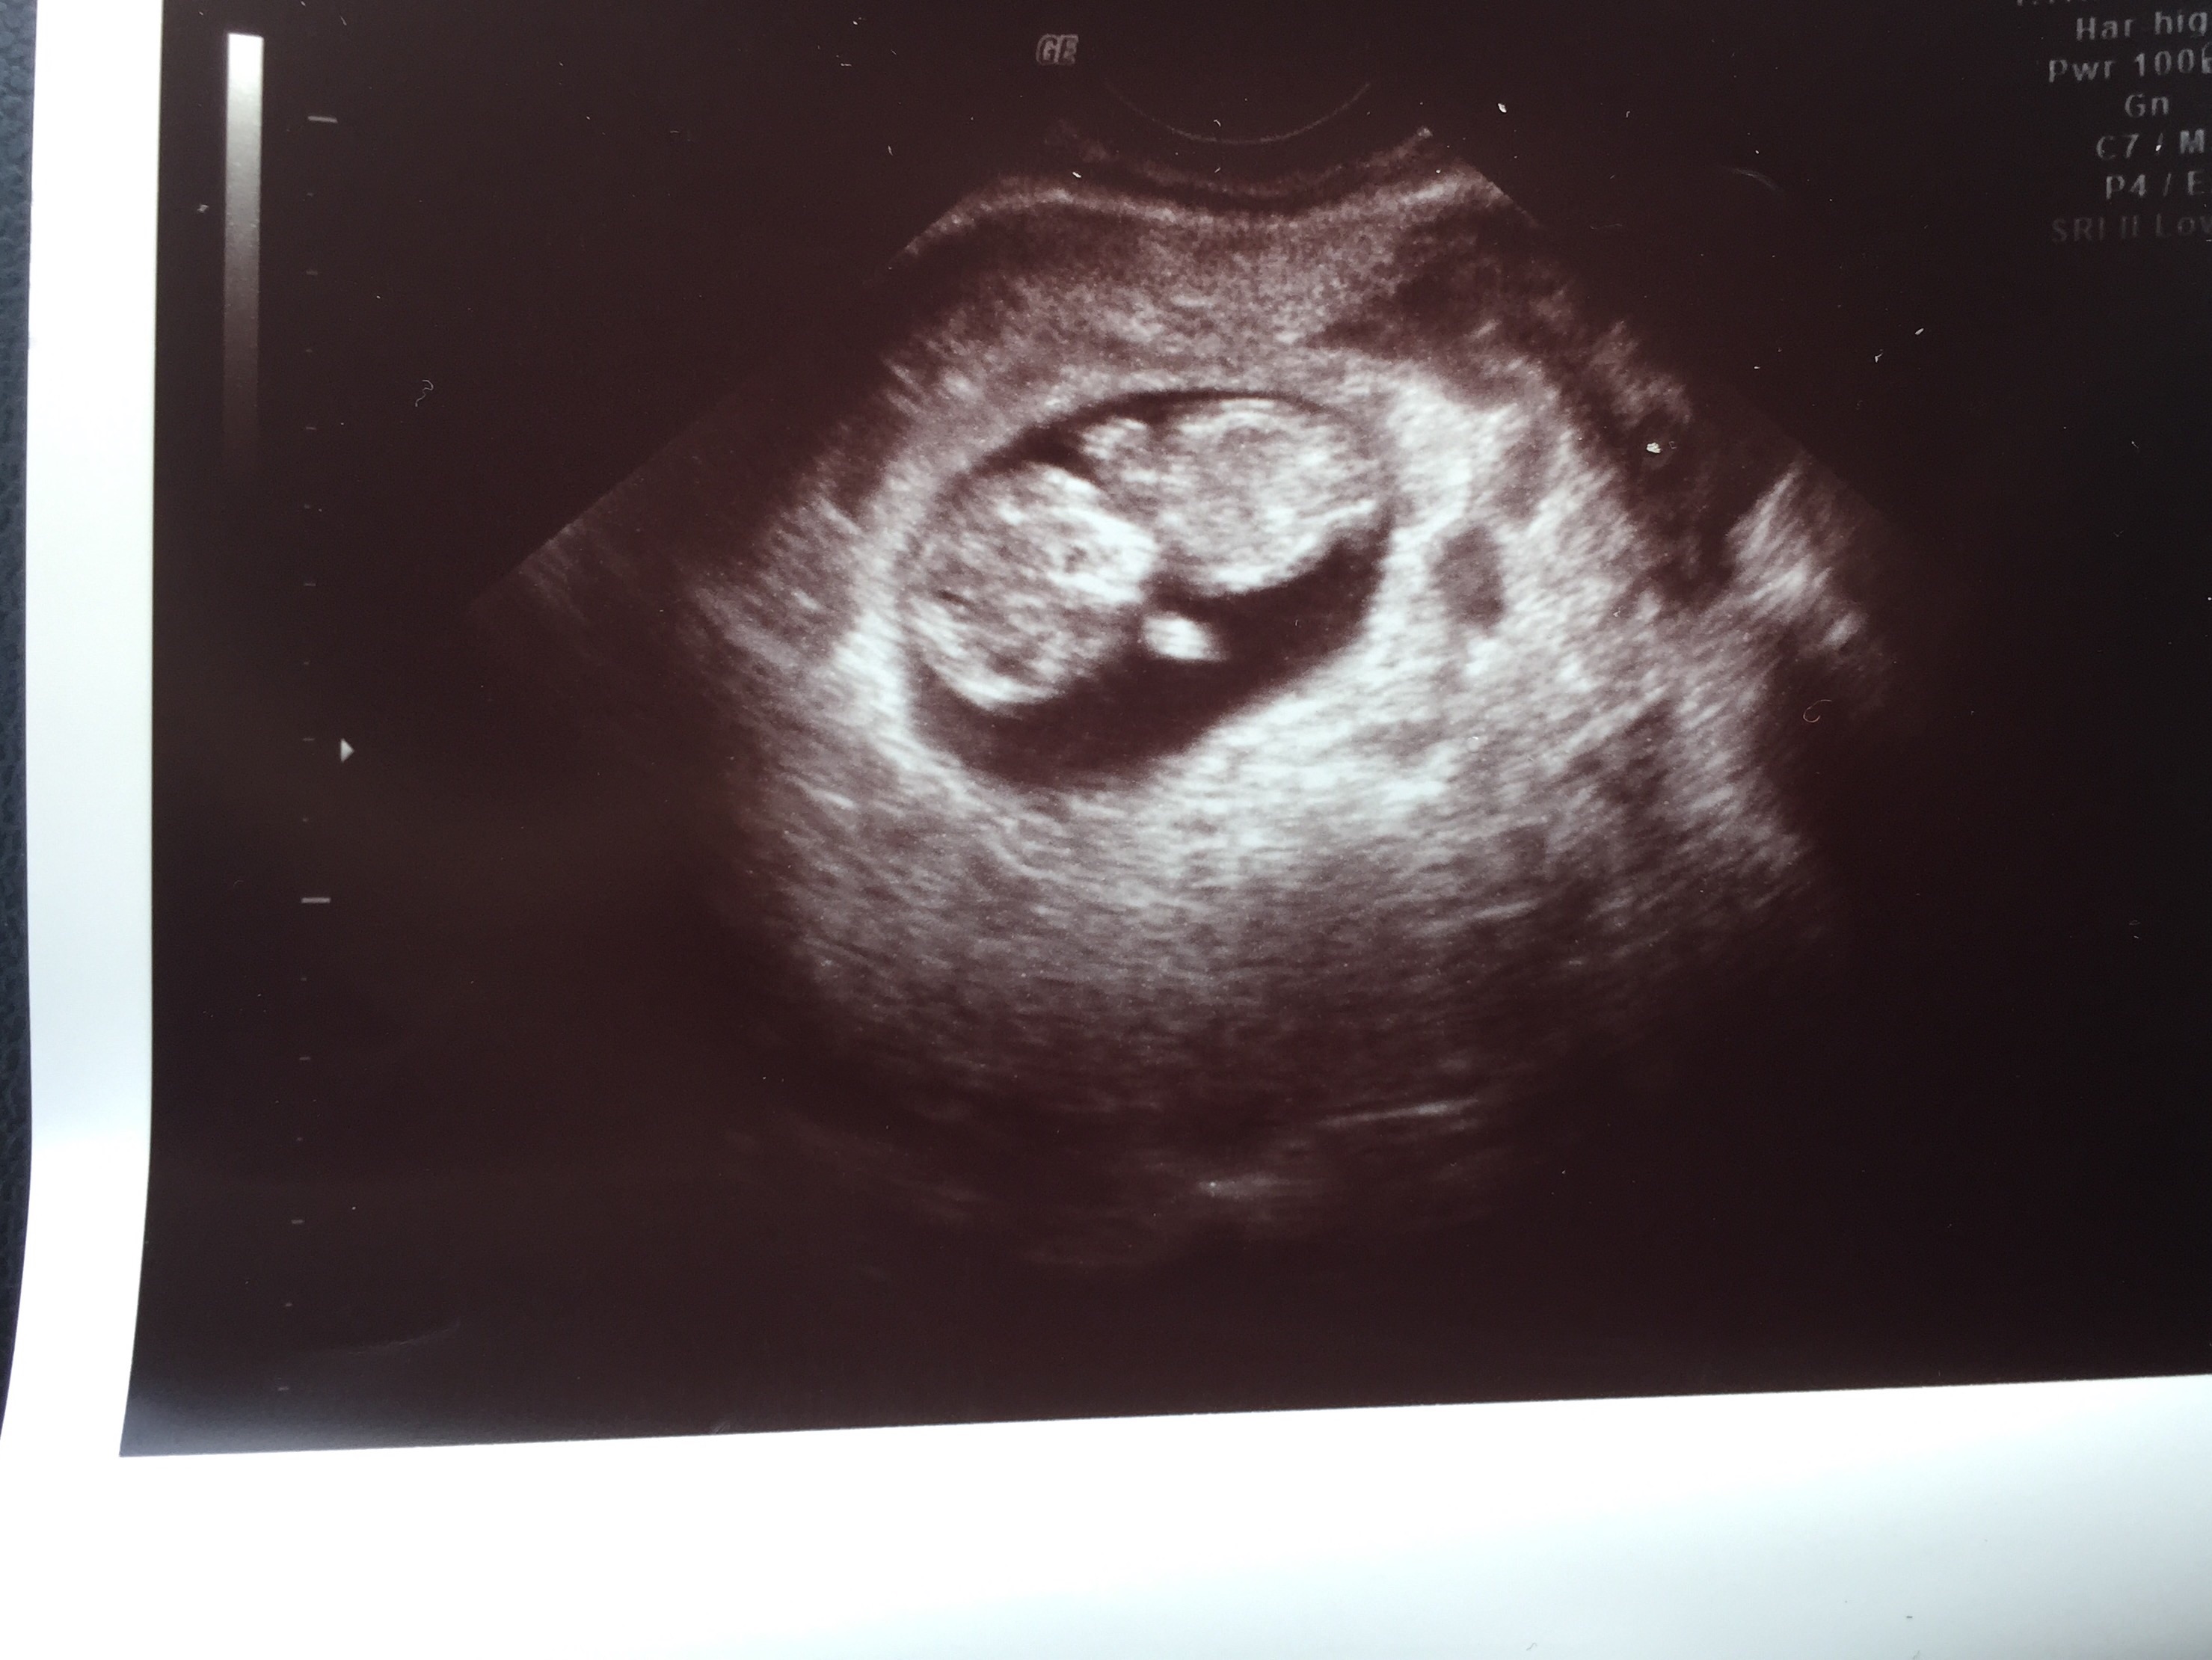

hey beautiful ladies how many of you have had your first ultrasound? How was your experience? I couldnt hold my tears when i saw the tiny being inside me with its heart beating. Such a wonderful thing to experience really:) my husband just couldnt hold smiling and looking away from the baby. Absolutely loved the experience. Here is the pic of the first ultrasound. The baby is 8 weeks 5 days as of today. Please share your experience. Would love to know